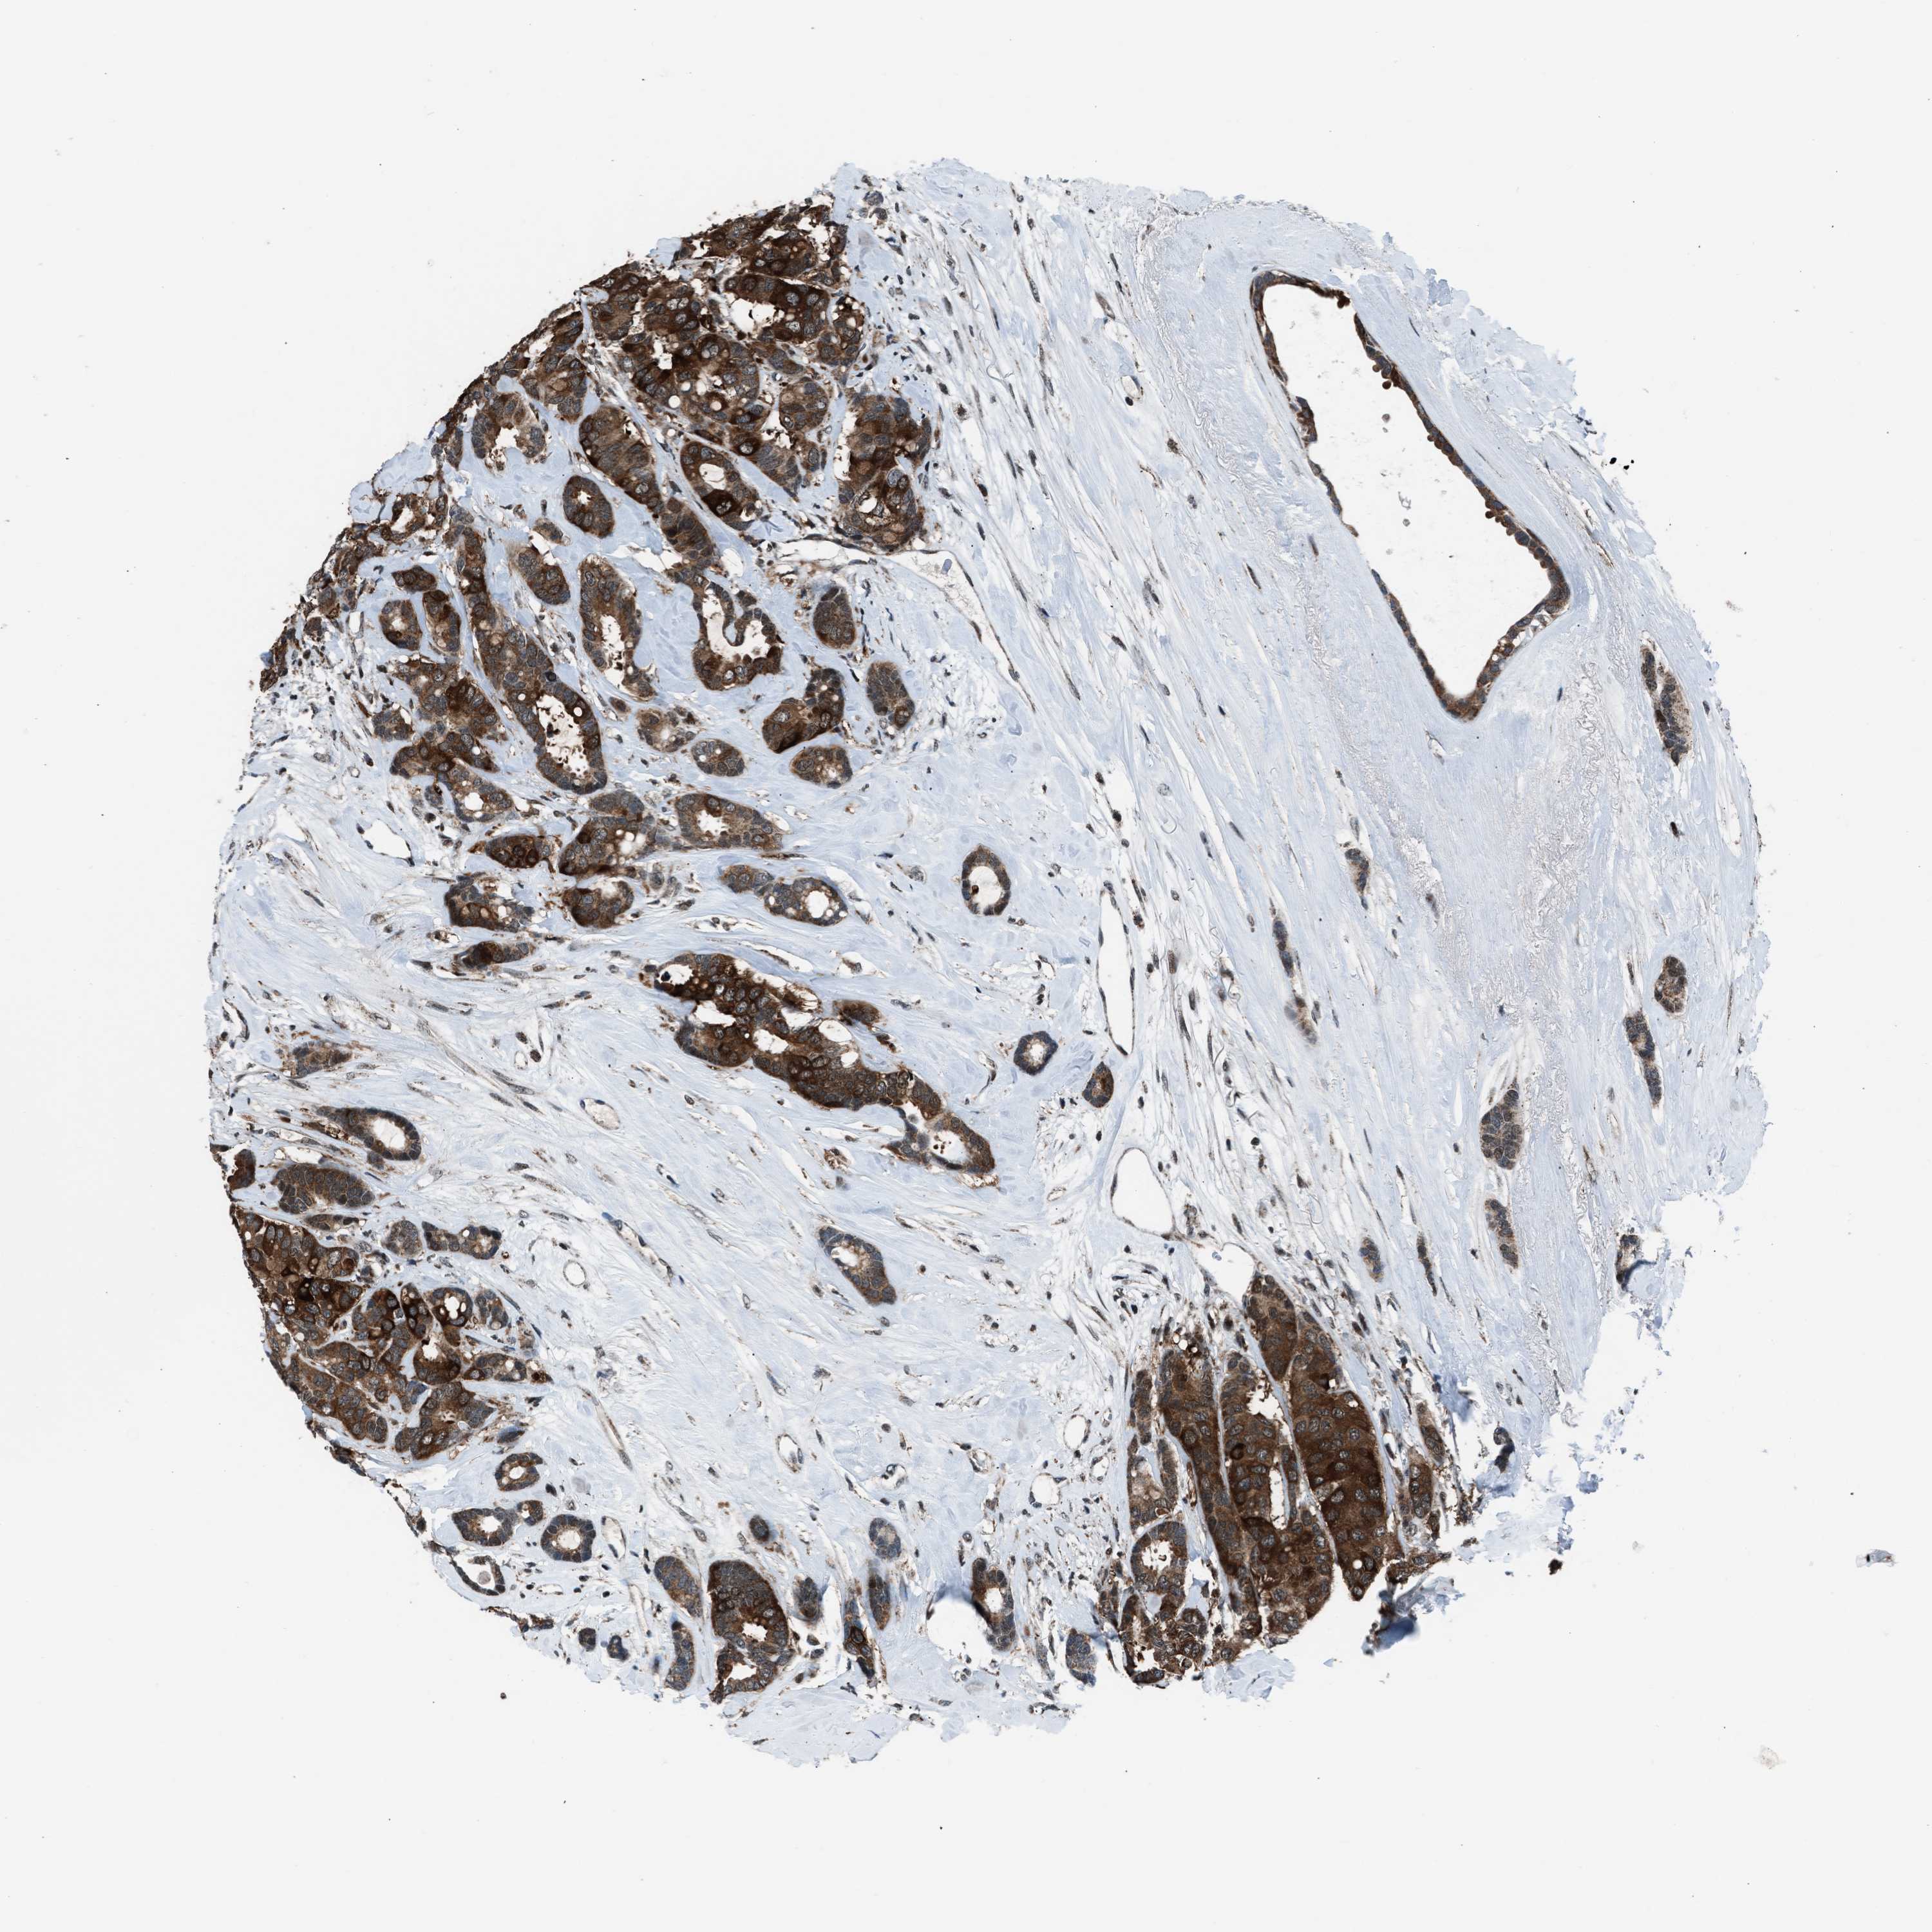

CANCER BREAST CANCER Show tissue menu

BRCA TCGA BRCA VALIDATION PROTEIN EXPRESSION